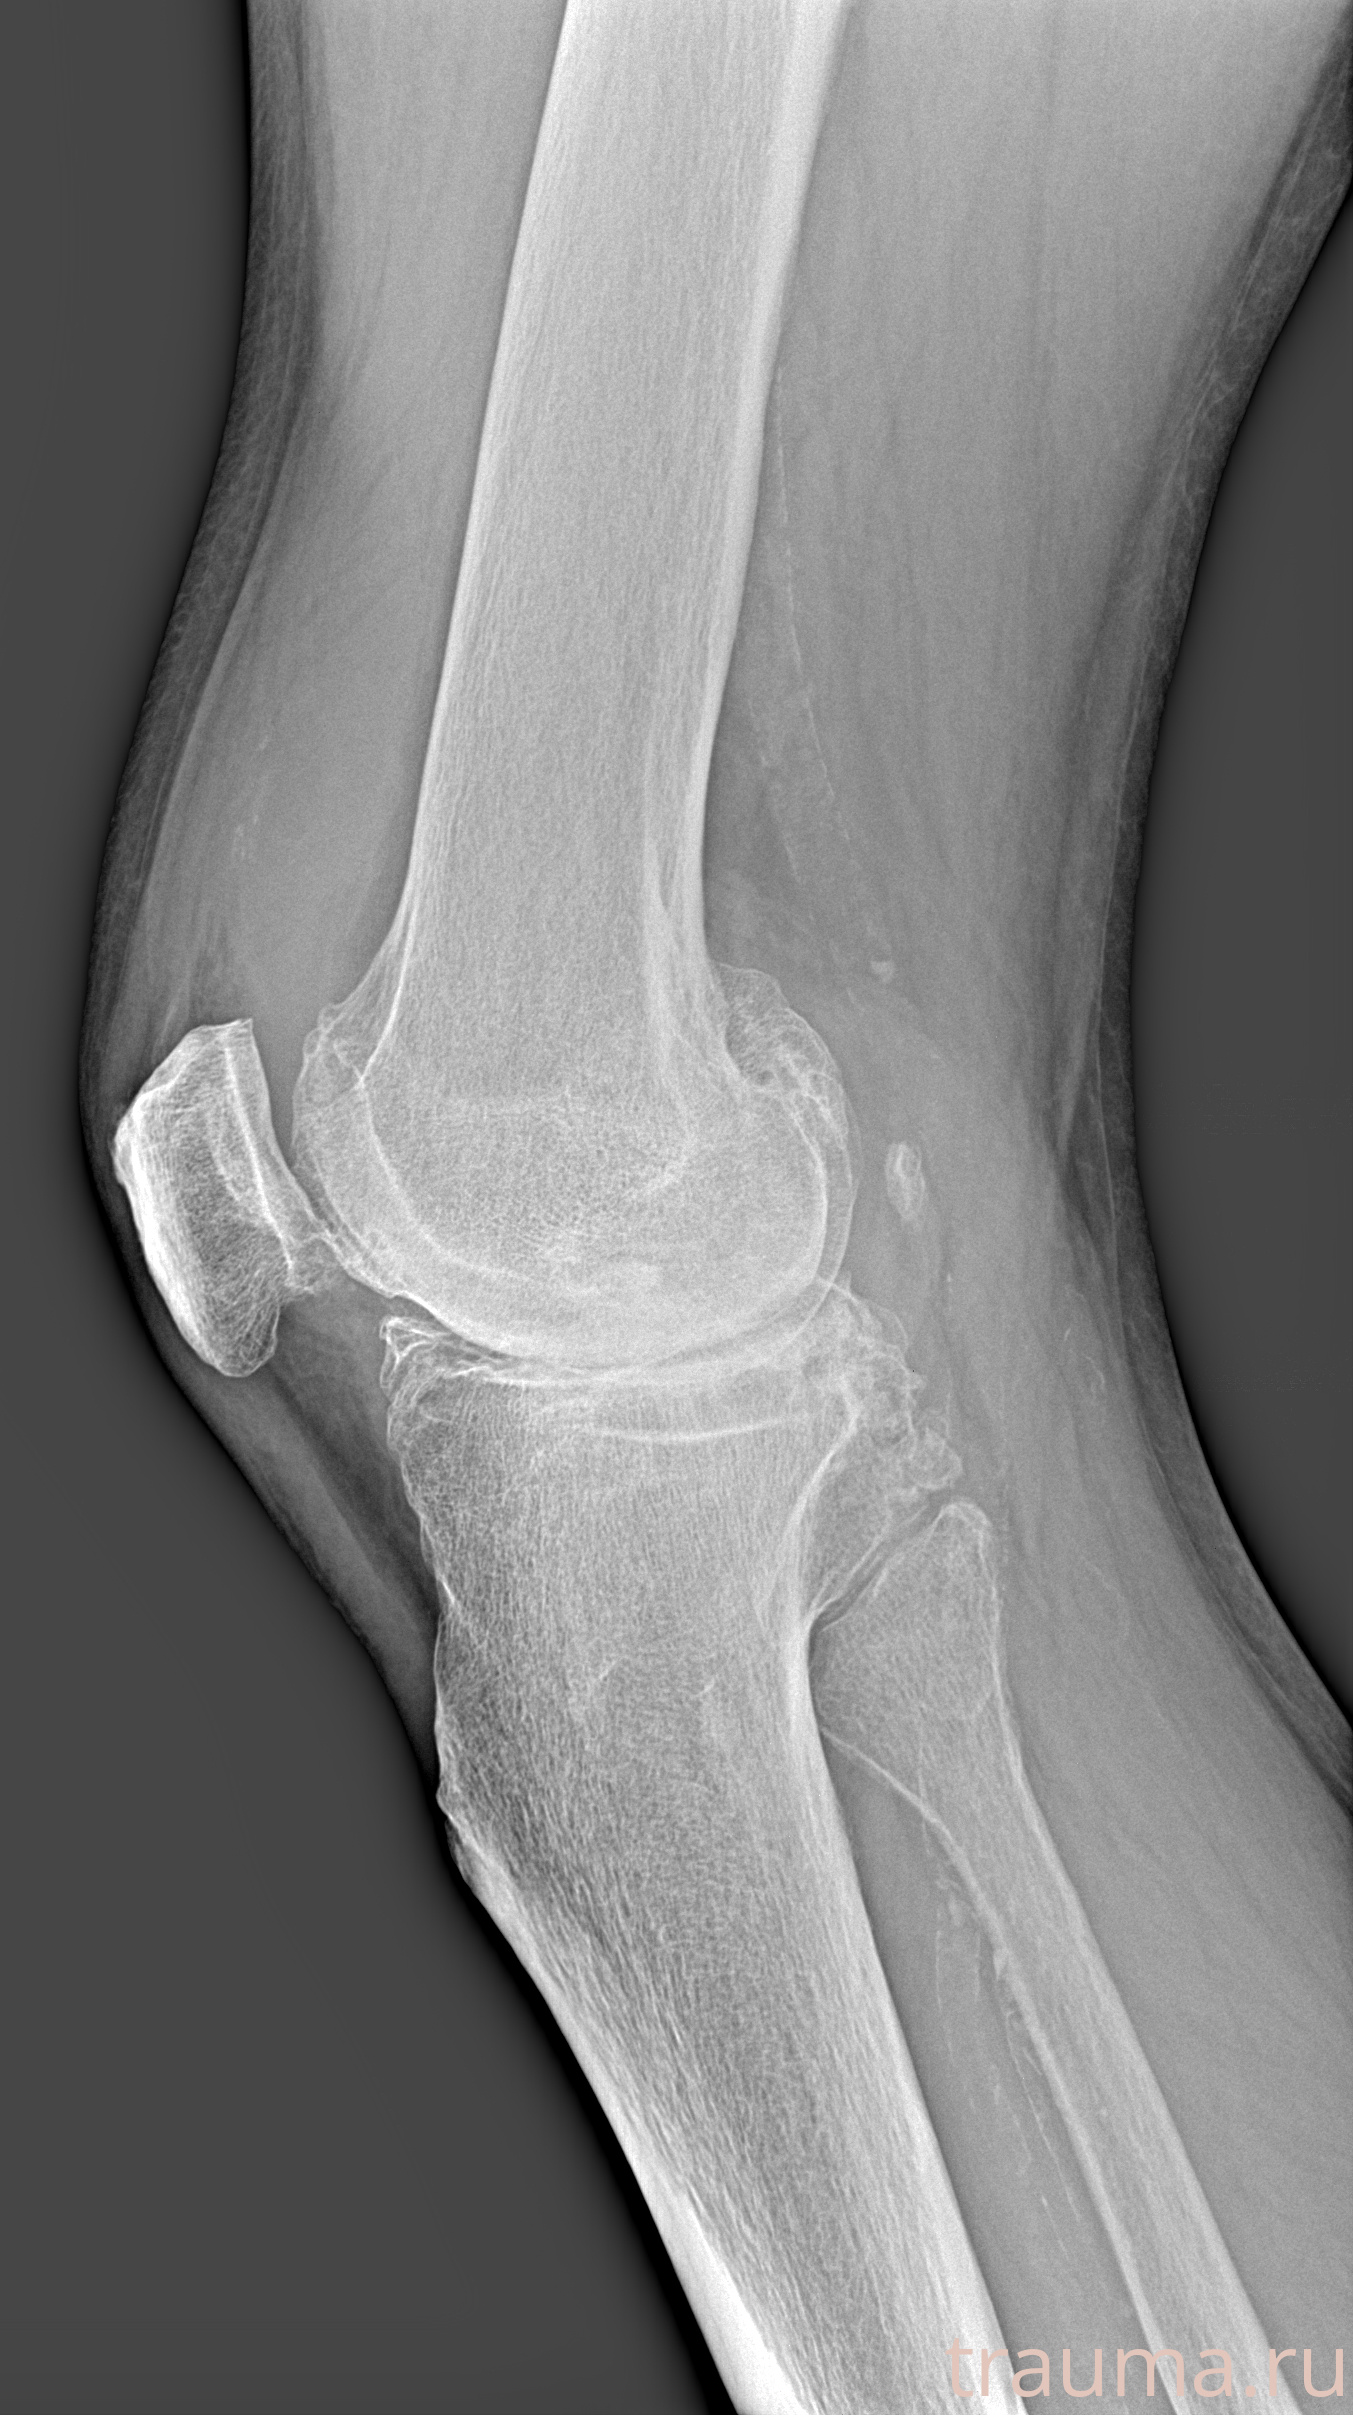

Рентген на дому: по вашему адресу приезжает врач-рентгенолог, травматолог-ортопед с мобильным рентгеновским аппаратом, проводит диагностику травмы или заболевания, делает необходимые рентгенограммы, дает рекомендации по дальнейшему лечению. Получить качественные снимки в домашних условиях возможно благодаря уникальной методике, разработанной МосРентген Центром для института  Склифосовского